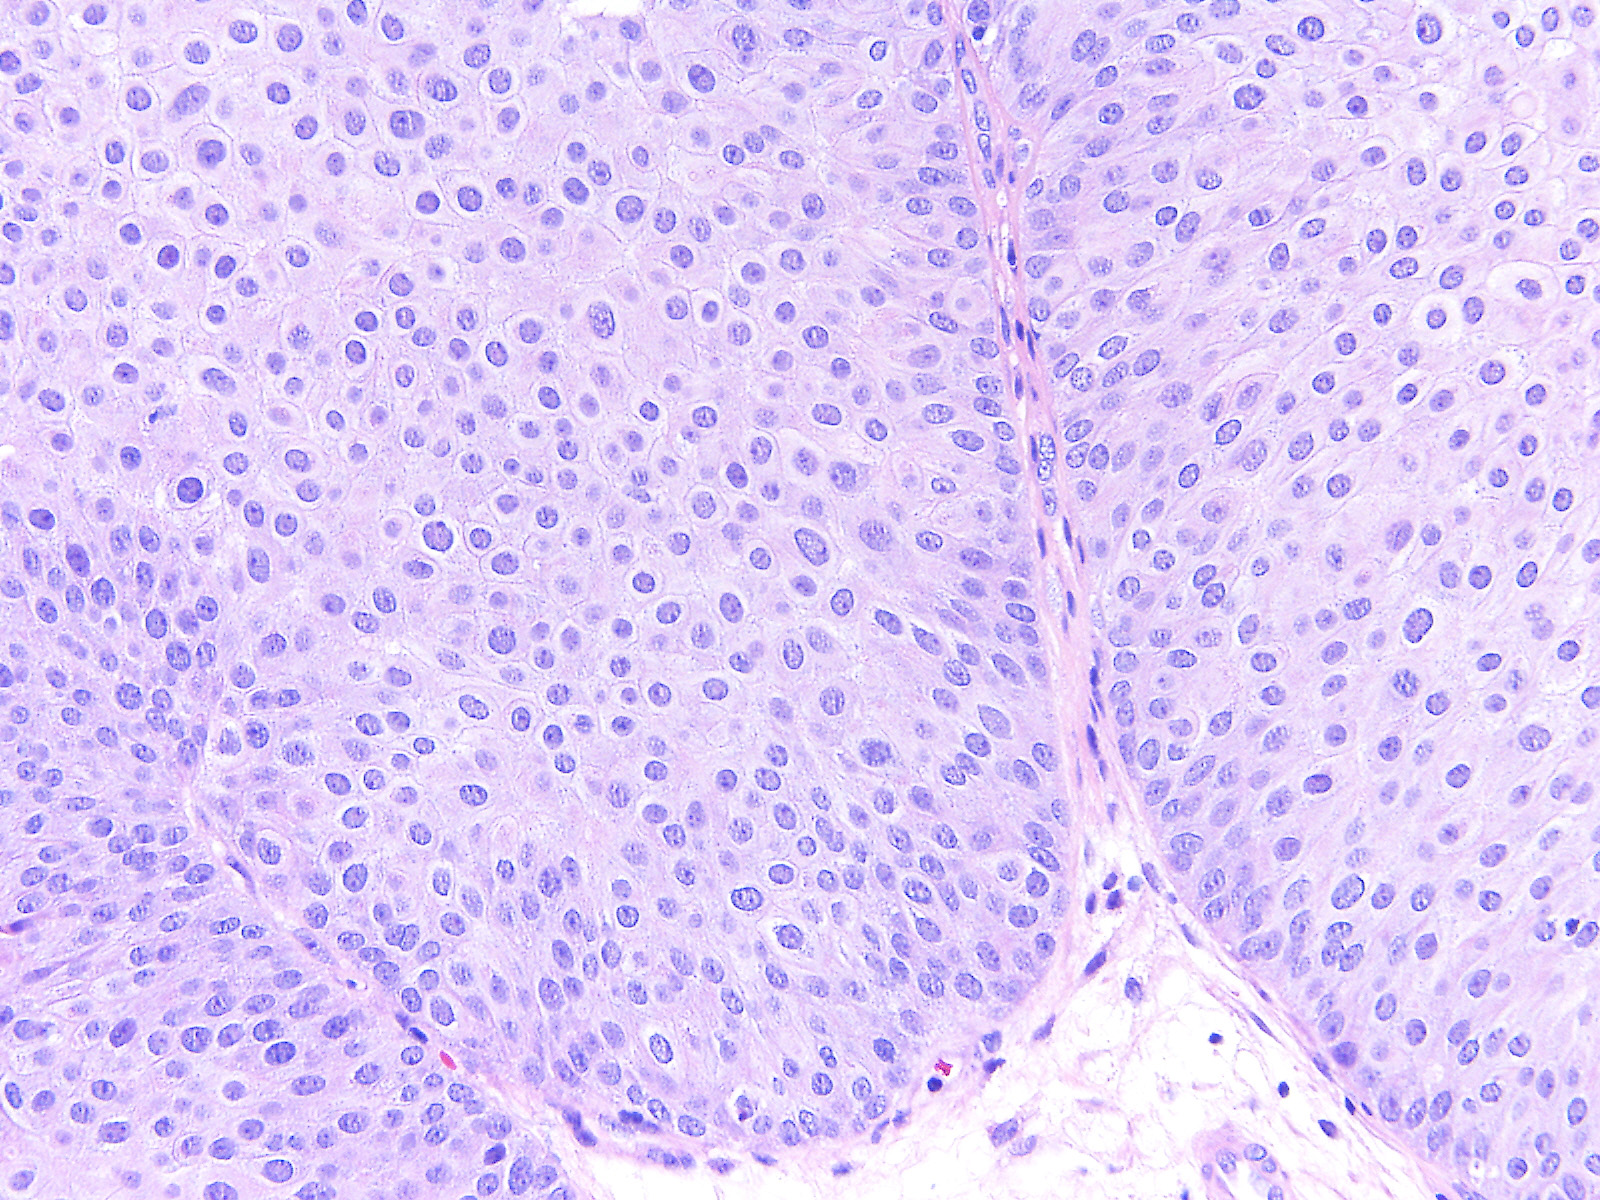

Bladder Papillary Lesions

Case ID: 526